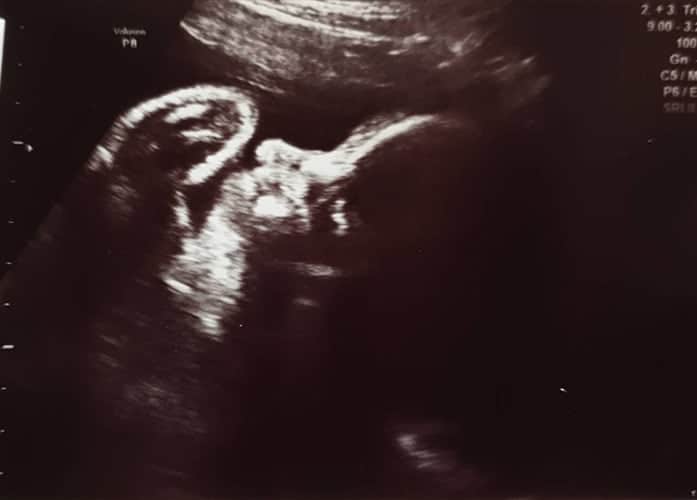

Ultraschallbilder aus dem 2. Trimester (13. bis 28. SSW)

Im 2. Trimester bekommt man oft die schönsten "Ganz-Körper" Ultraschallbilder. Das Baby ist nun so groß, dass man alles gut erkennen kann und noch nicht zu groß, so dass es noch ganz auf das Bild passt. In dieser Zeit lässt sich meist das Geschlecht bestimmen, wobei manche Babys es einfach nicht preis geben wollen und sich immer so drehen, dass man nichts erkennen kann.